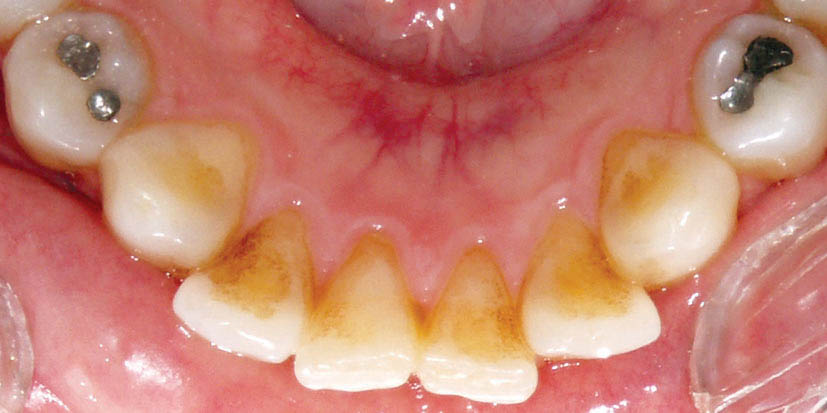

در شکل 170-1 میبینید که نیمه دیستالی لترالهای پایین به سمت لبیال چرخش دارد. ابتدا سیم 0.016 حرارتی گذاشته تا دندانها مرتب شوند، بعد آن را خارج میکنیم و روتیشنوج را روی انسیزورهایی که در قدیم چرخش داشتهاند (در این مورد دیستال لترالها میباشد) میگذاریم. دو سوراخ ریز روی آنها وجود دارد که باید درگیر دو بالچه مزیالی یا دیستالی کنید.

شکل 170-1: دیستال لترالهای پائین در ابتدای درمان به سمت لبیال هستند.

اگر در ابتدای درمان دیواره دیستالی به سمت لبیال چرخش داشته باشد باید روتیشنوج را بر روی بالچههای دیستالی بگذارید. اگر دیواره مزیالی به سمت لبیال چرخش داشته باید روتیشنوج را بر روی بالچههای مزیالی بگذارید، در این بیمار روی بالچههای دیستالی میگذاریم (شکل 171-1). بعد سیم 0.019x0.025 حرارتی را قرار دهید. شما نمیتوانید oring روی این براکت بیندازید، لذا وایر لیگاچور کنید. این روتیشنوج بایستی تا انتهای درمان بماند و همیشه روی براکت آن وایر لیگاچور شود (شکل 172-1). فقط در 4-2 هفته آخر که مرحله استقرار (فاز Settling) است باید آن را در بیاوریم تا قبل از خارج کردن براکتها، تمام دندانها مرتب باشند.

شکل 171-1: بعد از مرتب شدن انسیزور در شکل 166-1، روتیشن وج روی نیمه دیستالی میگذاریم، بعد آرچ وایر 0.019x0.025 حرارتی را روی آن قرار میدهیم تا باعث لینگوالی شدن بیشتر دیستال آن بشود.